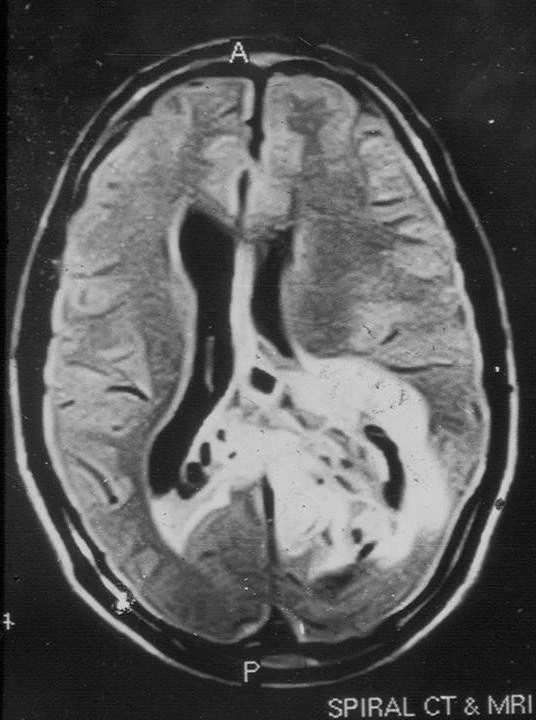

Figure 1 from Sudden blurring of vision and micropsia following acute ...

Case 10, male, 46 years old, left eye blurred for more than 5 months ...

Functional magnetic resonance imaging of a child with Alice in ...

Figure 1 from Functional MRI of a child with Alice in Wonderland ...